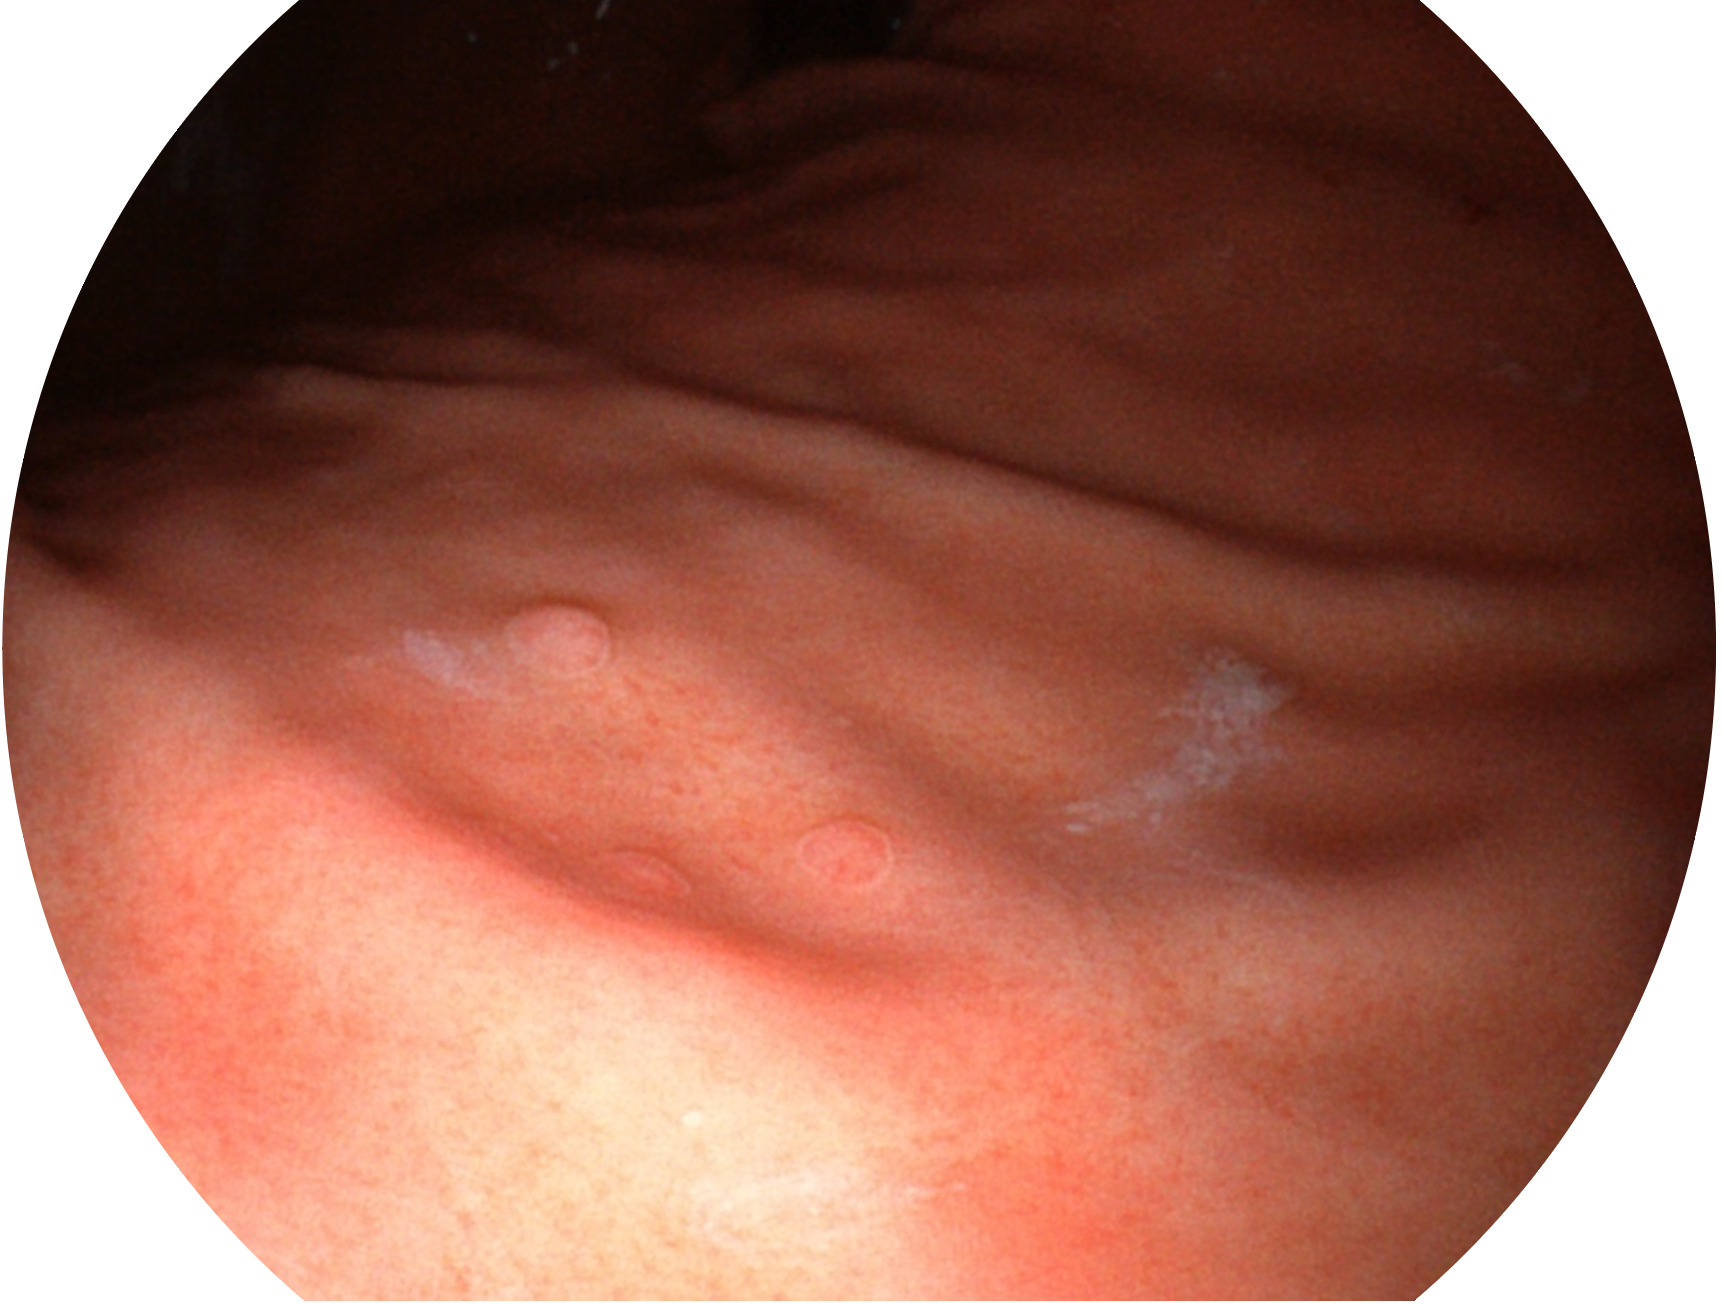

百老汇电子游戏官网新开发的内镜染色技术,主要是基于多波长LED 光源的开发,VLS-55Q 四波长LED 光源是由四个不同颜色的LED光按照相应照明模式所规定的特定发光比例进行合束后形成,合束后形成的照明光的光谱由红光、绿光、蓝光及蓝紫光这四个不同的波段范围构成。具有更高光谱自由度,通过光谱比例的控制,实现了聚谱成像技术,英文全称为“Spectral Focused Imaging, SFI”,缩写为“SFI”和光电复合染色成像技术,英文全称为“Versatile Intelligent Staining Technology, VIST”,缩写为“VIST”。